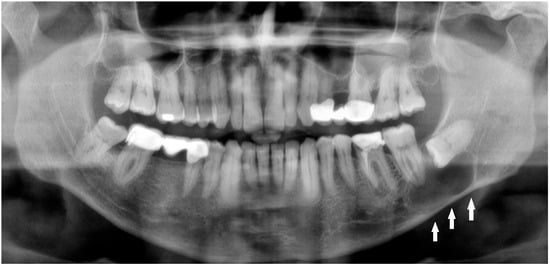

Dentigerous cysts (DCs), usually linked to unerupted teeth, are the second most common odontogenic cysts. However, synchronous DCs are rarely seen in children without syndromic conditions. This study reports two cases of male children with no systemic illnesses who showed multiple cystic lesions [...] Read more.

Dentigerous cysts (DCs), usually linked to unerupted teeth, are the second most common odontogenic cysts. However, synchronous DCs are rarely seen in children without syndromic conditions. This study reports two cases of male children with no systemic illnesses who showed multiple cystic lesions in the jaw. Conventional treatment typically involves enucleation and tooth extraction, which can lead to significant complications, including infection, nerve damage that may cause temporary or permanent numbness, damage to nearby teeth, and, in cases of large cysts, jaw fractures—potentially impacting the child’s quality of life. A conservative decompression method was used, employing custom-made tubes to keep communication between the cystic and oral cavities, thereby lowering intracystic pressure. This approach resulted in complete healing of the lesions and successful eruption of permanent teeth, while safeguarding vital anatomical structures and avoiding more invasive surgery, with an uneventful clinical course. Additionally, 3-year postoperative orthopantomograms are presented, showing complete resolution of the lesions with no recurrence. These results demonstrate the effectiveness of decompression in treating multiple dentigerous cysts in pediatric patients, highlighting its advantages in preserving oral function and aesthetics while reducing surgical risks. Full article

Figure 1